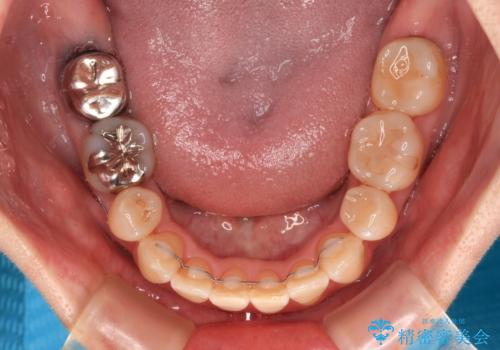

抜歯する第二小臼歯の後方の歯は神経近くにまで及ぶむし歯があったため、事前に処置をしておき、矯正治療後にオールセラミッククラウンにて補綴治療を行うこととしました。

第二小臼歯抜歯はイレギュラーな治療となるため、アンカースクリューを補助的に使用して、スムーズに治療を行えるように工夫をしました。